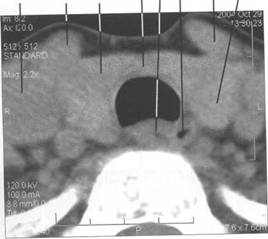

HU.